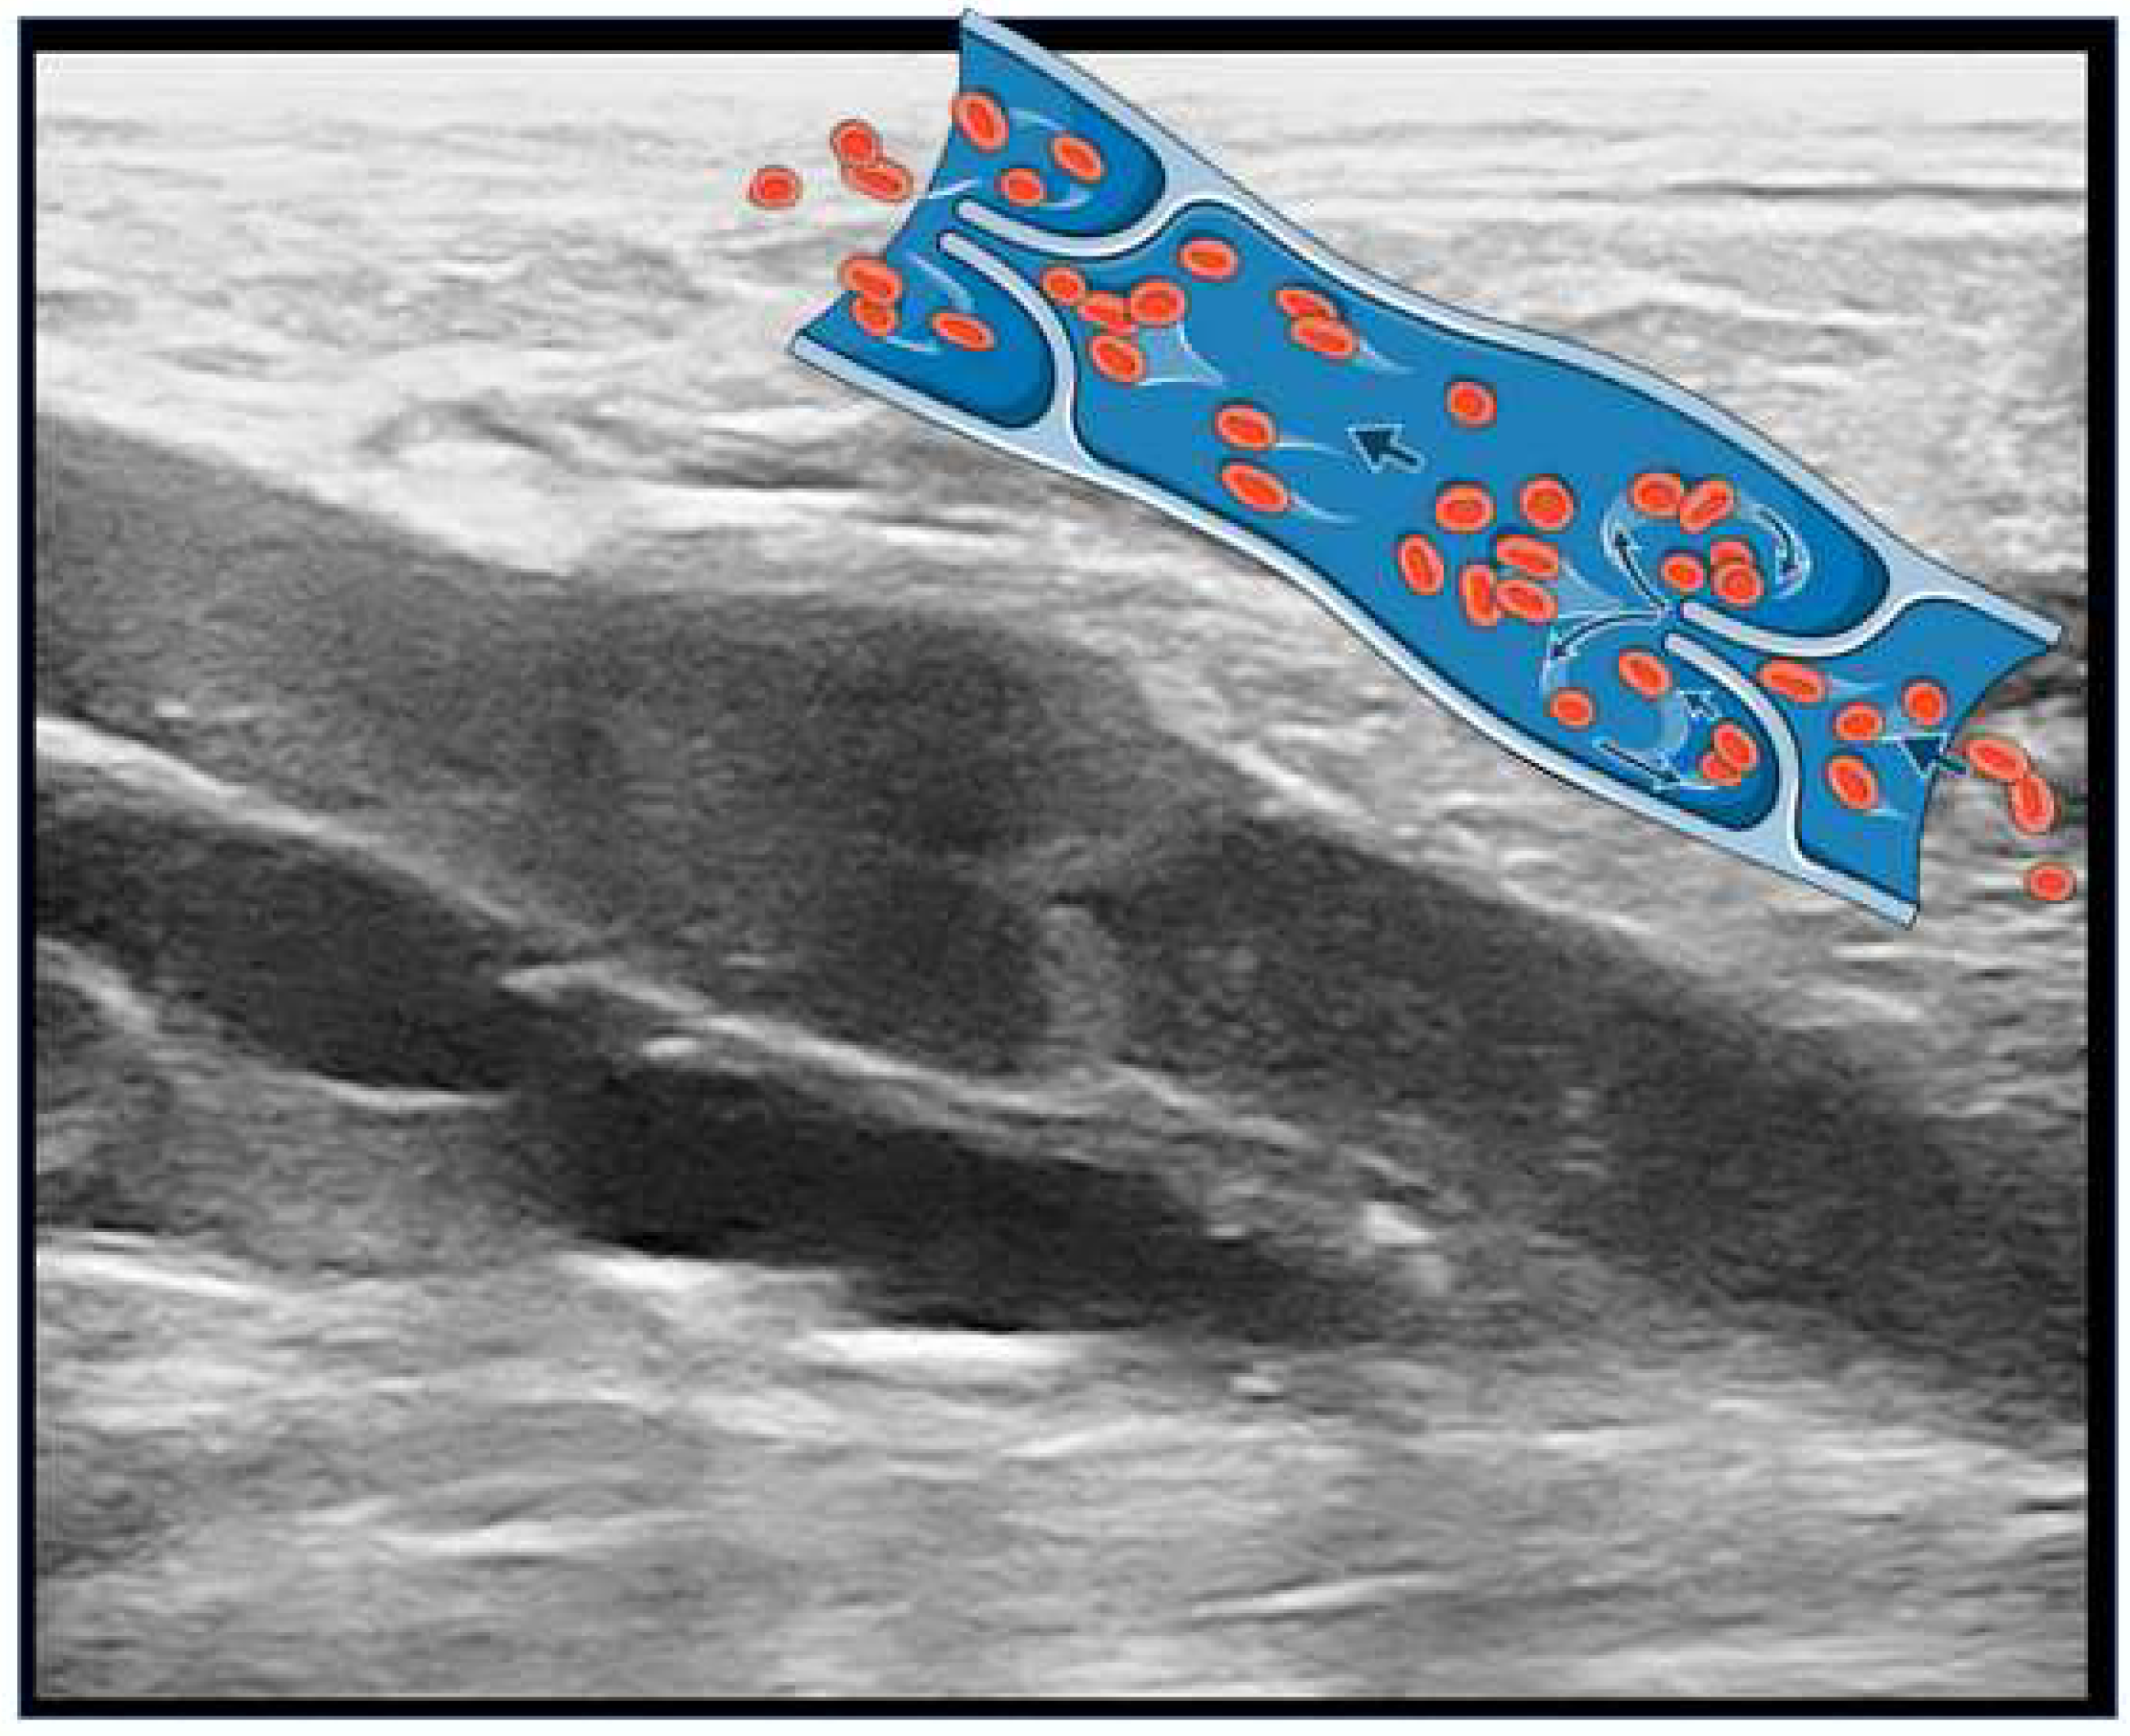

1.2. Doctor, What Is Chronic Venous Disease and What Are Varicose Veins?

1.4. How Is It Possible to Diagnose CVD?